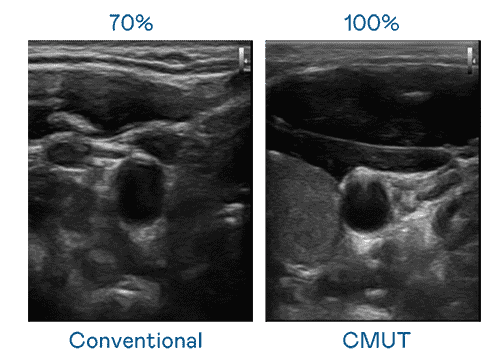

CMUT 技术是一种用电容式微机电元件来产生超音波讯号的技术。。。与传统 PZT 压电式技术相比,,,,CMUT 频宽增加 30%,,,,更宽频的超音波讯号让影像解析度大幅提升,,是实现高影像品质医疗超音波扫描、、促进精准医疗发展的关键技术。。

大频宽带来超清晰影像

超音波影像的解析度高低,,首先取决于探头能发出的讯号频宽。。彩霸王 CMUT 可提供高清晰的超音波讯号,,,提供高频宽、、、、高灵敏度、、影像纹理细节更高的超音波影像,,协助医护人员缩短影像判读时间及利用精准的医疗影像进行诊断。。